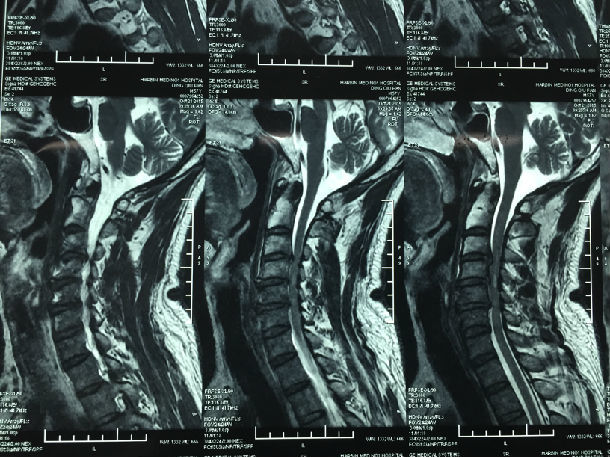

手术前-多节段颈椎间盘突出/黄韧带肥厚/颈椎管狭窄-脊髓损伤

手术前-颈髓明显受压伴脊髓损伤

显微镜下微创手术后-颈椎管明显增宽/脊髓受压解除/患者症状迅速好转